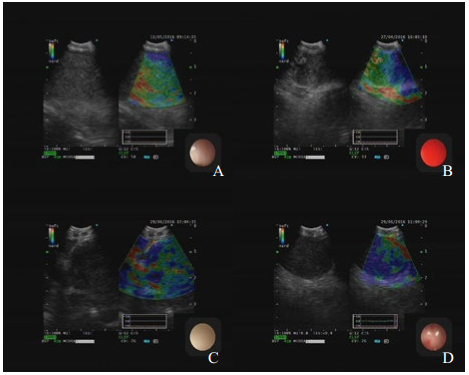

1.2 检查仪器和方法 1.2.1 检查方法(1) 术前要求禁食至少8 h;(2)麻醉方法:采用全凭静脉麻醉(total intravenous anaesthesia,TIVA),即以瑞芬太尼0.5 mg镇痛,配合咪唑安定10 mg和艾贝宁200 μg镇静,外加口咽通气管,保留自主通气的办法,至睫毛反射消失后行支气管镜检查,术中若烦躁明显可追加剂量至满意[11];(3)经鼻或口腔以常规电子支气管镜(型号1T260)检查;(4)再以超声支气管镜(型号奥林巴斯BF-UC260FW)前端置有探头水囊(型号MAJ-1351)在气管腔内观察淋巴结的位置及大小等;(5)常规超声检查目标淋巴结位置、直径等信息,并在同一层面行弹性成像(典型图像见图 1);(6)确定穿刺淋巴结后,在超声实时引导下,以奥林巴斯穿刺针(型号NA-201SX-4021或NA-201SX-4022)进行穿刺,每个淋巴结部位平均穿刺2-3针,获得满意组织病理为止;(7)获取的组织送检做病理学及细胞学检查。

| A淋巴结回声中等,边界不清,回声均,大小23.4 mm×20.3 mm,弹性评分1分,EBUS-TBNA病理示结核;B淋巴结回声中等,边界不清,回声不均,大小16.9 mm×25.6 mm,弹性评分2分,EBUS-TBNA病理示结节病,C淋巴结低回声,边界清,回声不均,大小27 mm×36.4 mm,弹性评分3分,EBUS-TBNA病理示腺癌,D淋巴结低回声,边界清,回声均,大小32 mm×37.7 mm,弹性评分4分,EBUS-TBNA病理示小细胞肺癌 图 1 典型淋巴结常规超声及USE图像 |

通过软件收集弹性成像图片(JPEG图像),使用image-J软件计算出蓝色区域占淋巴结区域比值,进行弹性成像评分。评分标准[12]:①1分:小于20%的切面显示为蓝色;②2分:20%~50%的切面显示蓝色;③3分:50%~80%的切面显示为蓝色;④4分:超过80%的切面显示为蓝色。见图 1。